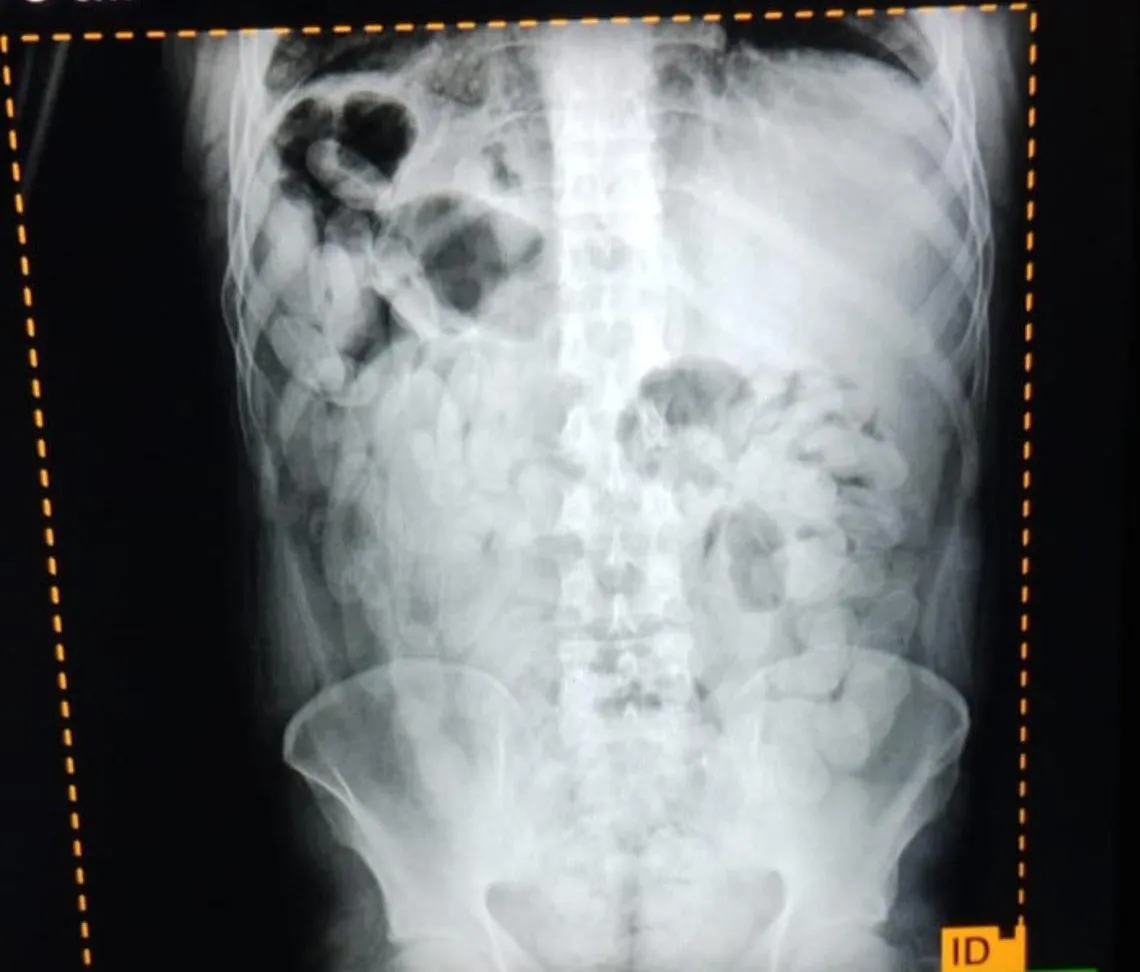

Mediante estudios radiográficos, el personal médico confirmó la presencia de múltiples cuerpos extraños en el sistema digestivo de los individuos, compatibles con cápsulas de estupefacientes. Posteriormente, los involucrados evacuaron un total de 180 cápsulas, las cuales fueron sometidas a la prueba de campo narcotest, arrojando resultado positivo para cocaína.